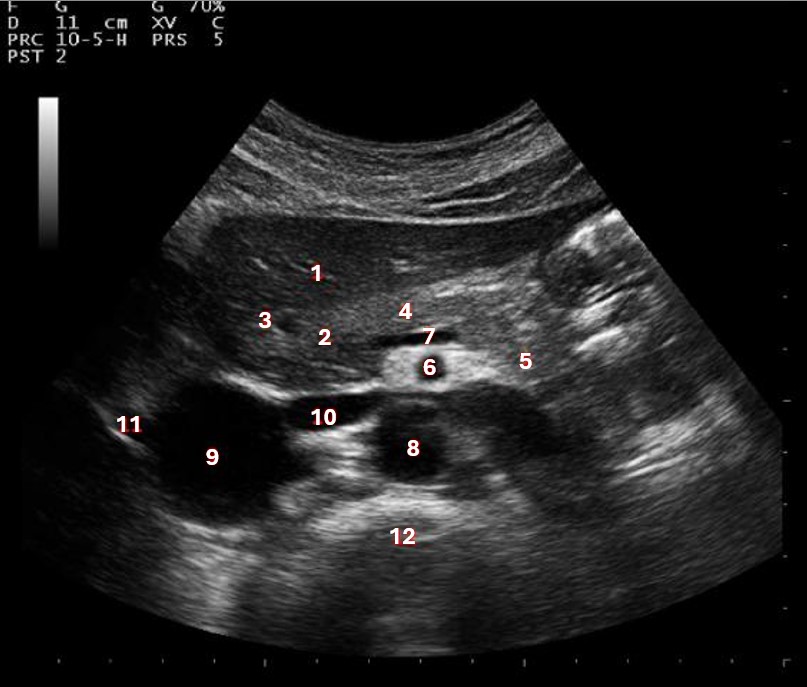

Which of the following structures is labeled #5?

lateral left lobe |

What lobe of the liver is indicated by #1?

posterior right lobe

What structure/vessel is indicated by #8?

medial left lobe |

What lobe of the liver is indicated by #2?

anterior right lobe |

Which of the following structures is labeled #1?

Which of the following structures is labeled #7?

anterior right lobe |

What structure/vessel is indicated by #12?

spine

Which of the following structures is labeled #6?

medial left lobe |

Which of the following structures is labeled #3?

IVC

Which of the following structures is labeled #8?

posterior right lobe |